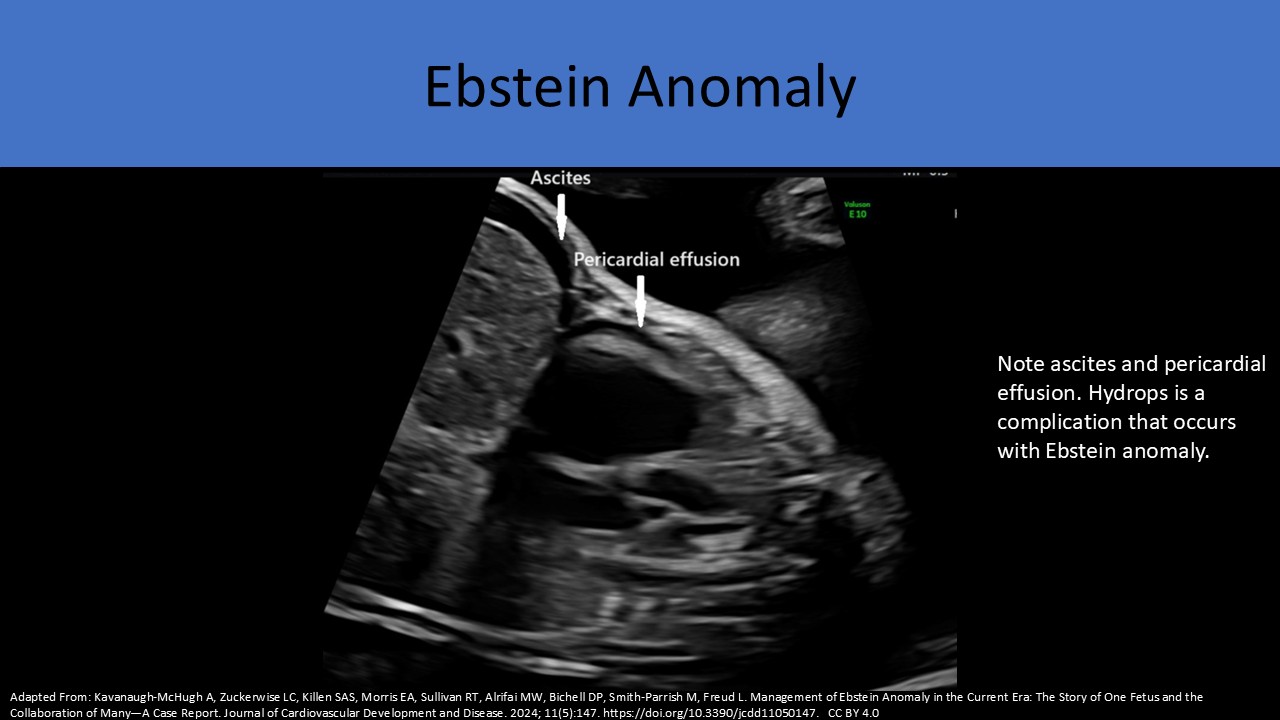

Frequently diagnosed in utero because of the associated cardiomegaly, hydrops and SVT

Usually results in severe cardiomegaly, hydrops and tachyarrhythmias

Restrictive interatrial shunting through the foramen ovale leads to fetal hydrops and demise

Progressive cardiomegaly is a common complication with valvular regurgitation

Serial exams are performed to detect signs of progressive heart failure and the development of hydrops